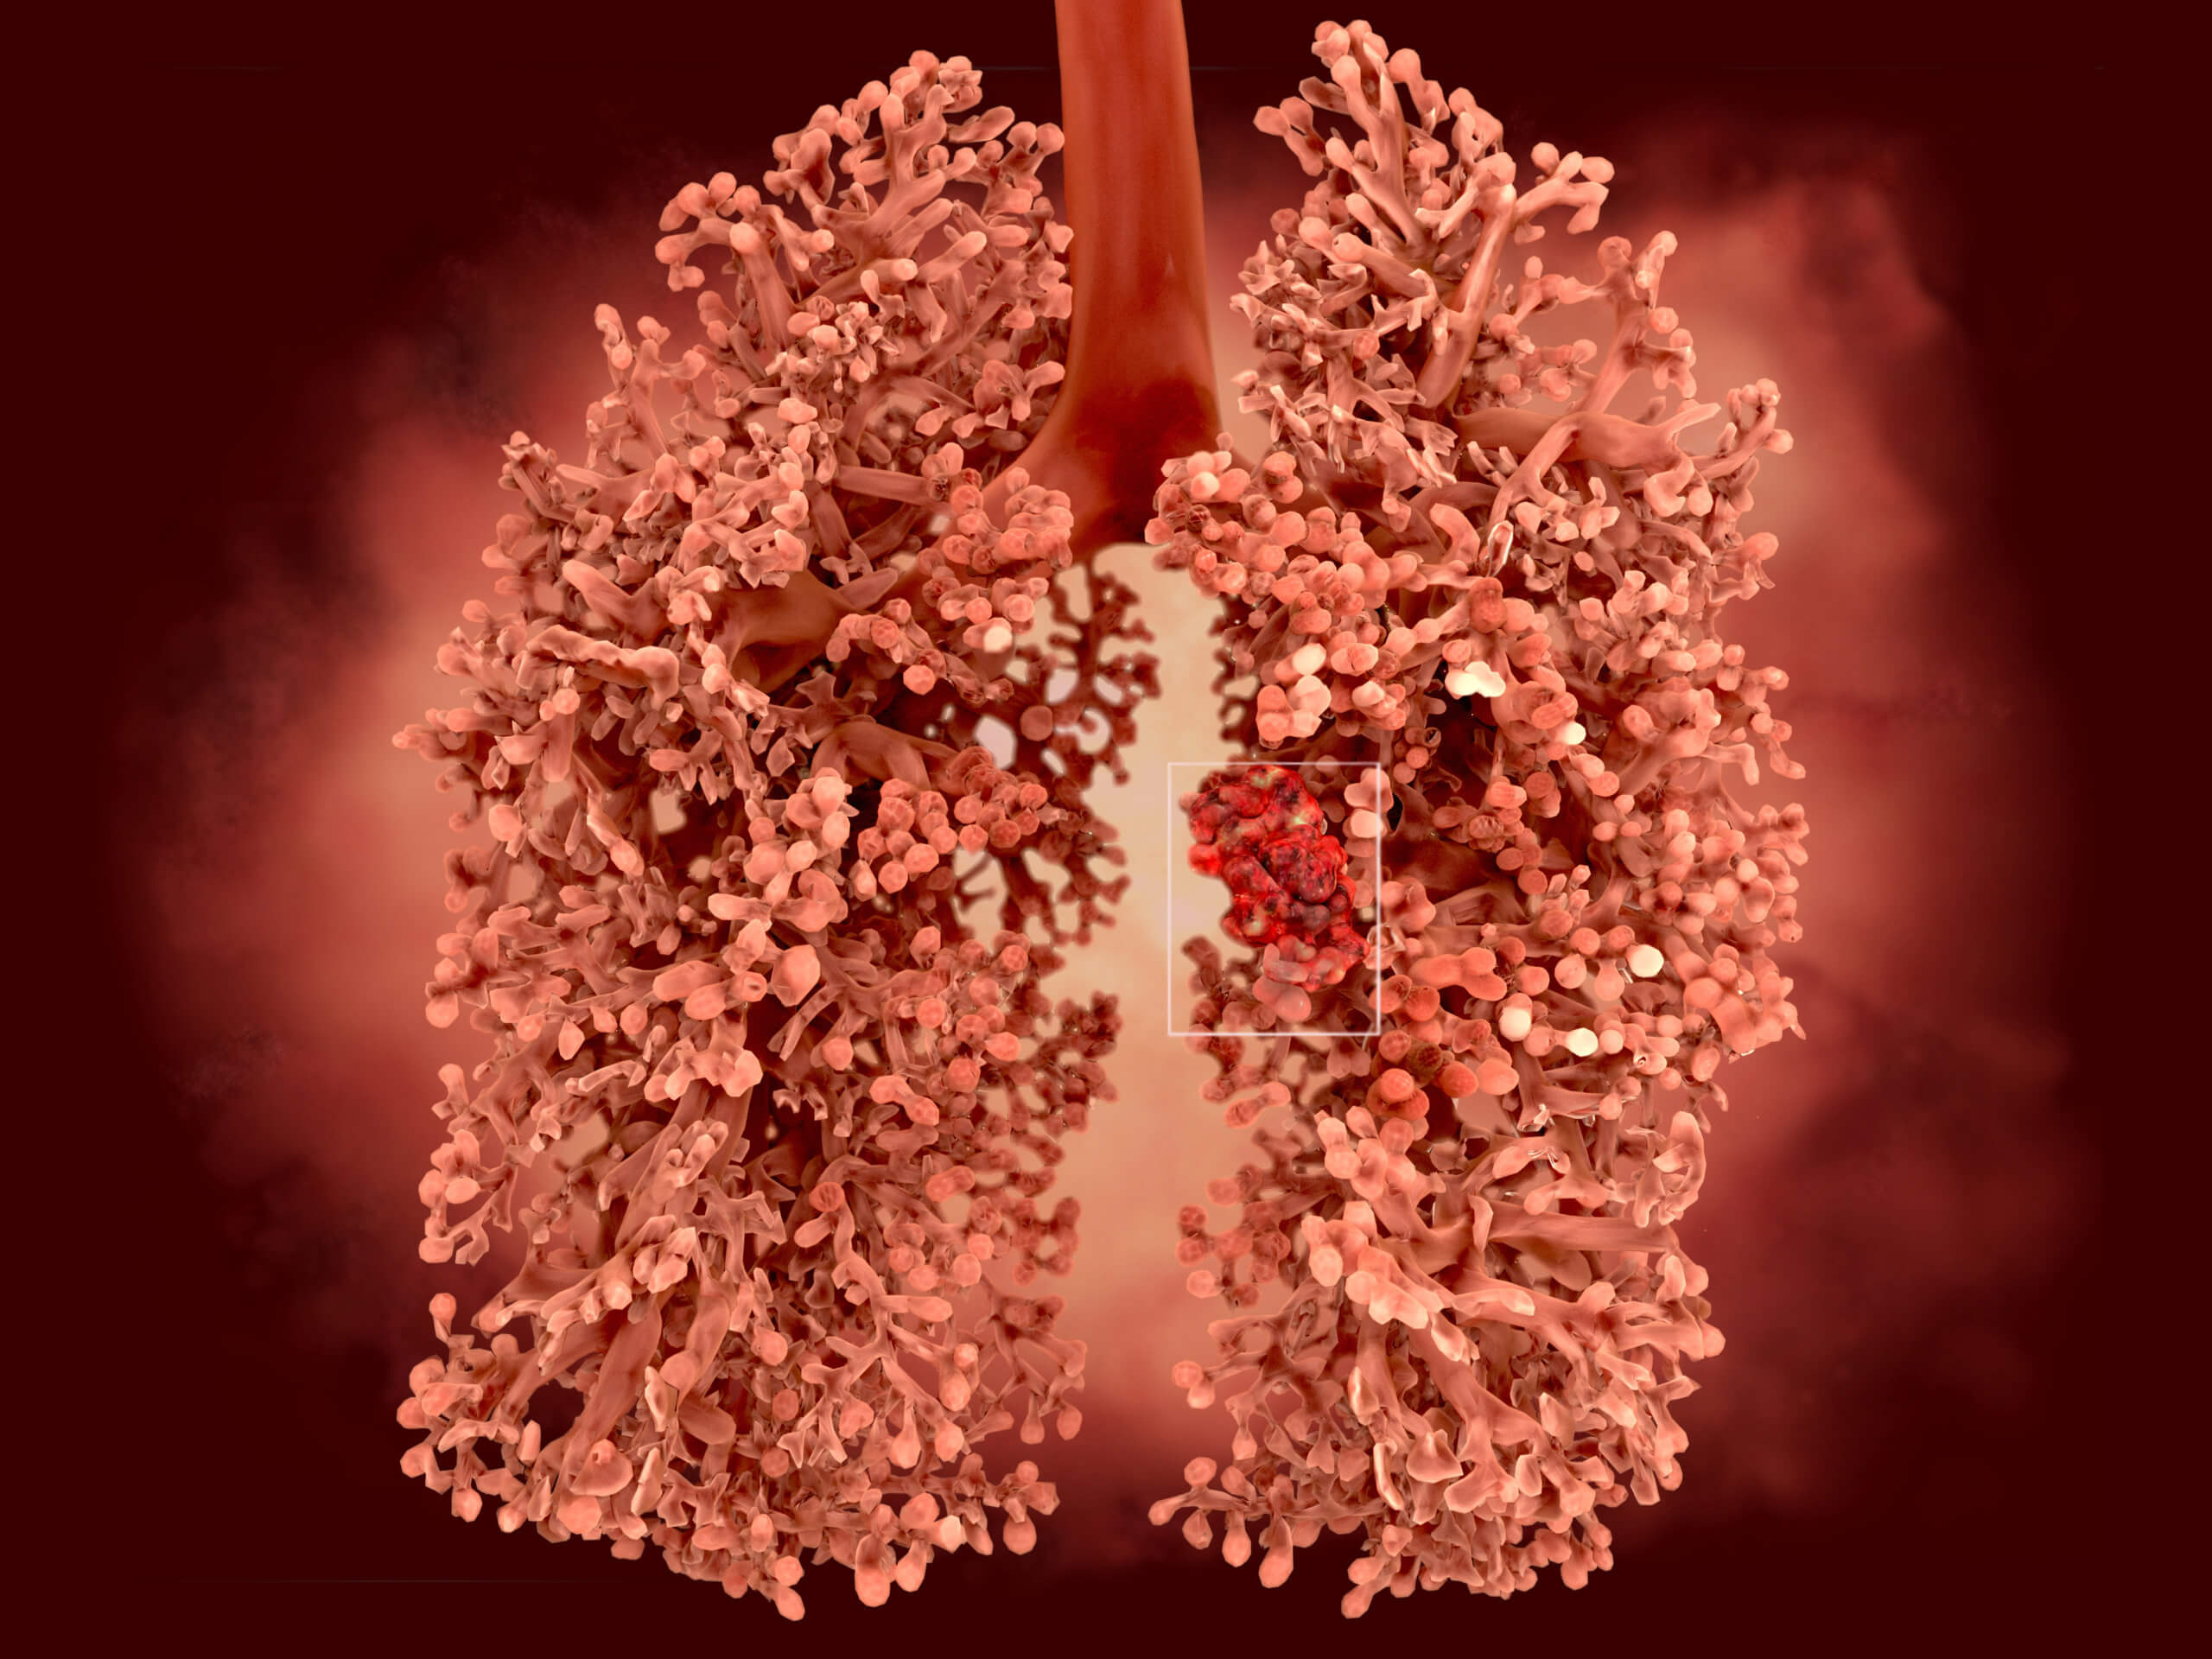

Фото Легких После Вейпа 107 фотографий